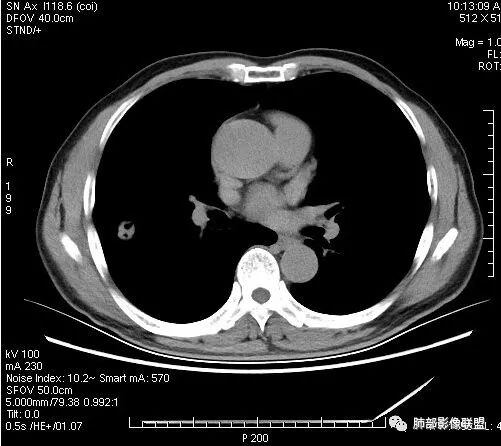

影像学改变:

1.右肺上叶后段类圆形结节影,密度不均,有坏死空洞,坏死比较彻底,内外壁都较清楚。

2.病灶有浅切迹,没有深分叶,毛刺大多细长且柔软。

3.可见棘状突起及胸膜牵拉,但未见胸膜凹陷。

什么意思?结节影有牵拉的动作,但似乎“出工不出力”,收缩力羸弱!

4.病灶轻到中度强化。病灶内血管走行较完好,病灶旁血管局部显示粗大。

5.支气管关系不确定。

6.灶周见小结节影(卫星灶),边界不甚清晰。